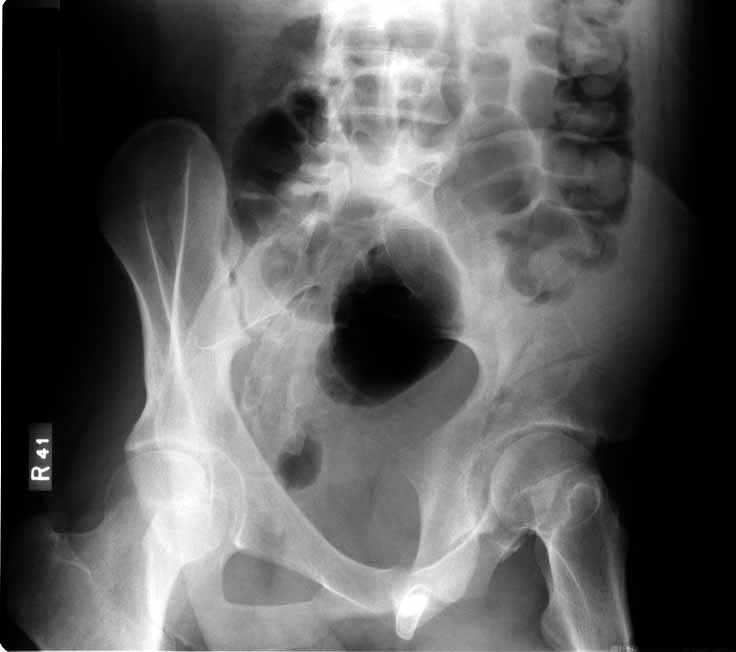

Subject: Acetabular Fx - both columns

This is an 18 yo male involved in an MVA 2 days ago. Isolated injury other than some rib fxs. I had trouble interpreting the xrays, but the CT shows a both column fracture with secondary congruence (I think). The plain films show significant gapping of the anterior column, but the CT shows fairly little at the dome.

Reducing the anterior column should be straightforward through the ilioinguinal approach, but will the piece of the posterior column articular surface go with it, and if it doesn't will this be reducible after reducing the anterior component? Or is this true secondary congruence and what are the consequences of letting it heal as is?

You'll notice that the anterior column is incomplete peripherally...this lends stability if you elect to treat him without surgery, and indicates an osteotomy at the iliac crest to complete the fracture and allow its mobilization for cleaning and reduction, should you choose surgery.

In my opinion, he will do well treated nonoperatively, and I have many similar cases in my practice with favorable followup. As Chip points out, the anterior column is incomplete peripherally, thus very stable in its current position. These are very hard to move intra operatively until the fracture is completed. Nonoperative Rx does carry a slight chance of further displacement, so close followup is needed. If I did anything operative, it would be a perc screw from anterior to posterior to secure the dome reduction. This can be done using the iliac wing view that profiles the "teardrop" to target the screw.